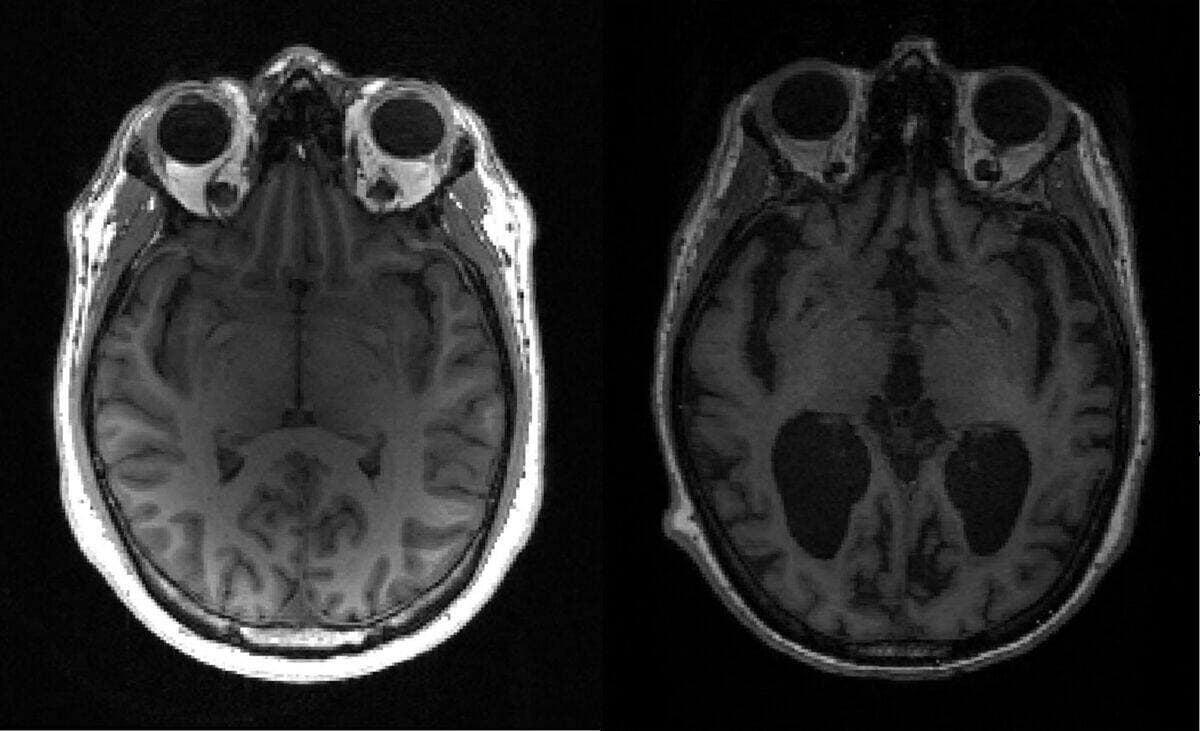

À l'aide de l'électroencéphalographie (EEG) et de l'imagerie par résonance magnétique fonctionnelle (IRM), les scientifiques ont enregistré l'activité cérébrale des participants avant, pendant et après l'administration de la drogue. Les volontaires ont aussi fourni des informations sur l’intensité de l’expérience vécue après avoir consommé la puissante substance.

Les données révèlent de profonds changements sur l'ensemble du cerveau, particulièrement dans les zones les plus évoluées chez l’humain, qui jouent un rôle dans la planification, le langage, la mémoire, la prise de décisions complexes et l'imagination.

Les régions cérébrales à partir desquelles on conçoit la réalité se mélangent et deviennent hyperconnectées, ce qui rend les communications entre elles plus chaotiques, mais aussi plus fluides, selon les chercheurs.

Plus la dose prise est élevée, plus l’intensité de l’expérience est forte et plus des zones cérébrales sont hyperconnectées.